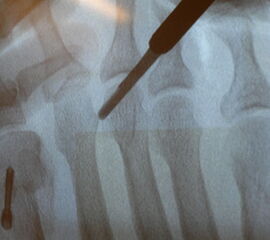

Jetzt erfolgt das Einbringen der Fräse im 45°-Winkel von distal dorsal nach proximal plantar. Auf steten Knochenkontakt mit der Kortikalis zur Vermeidung eines Weichteilinterponates sollte geachtet werden. In unserer Abteilung erfolgt vor Beginn der Osteotomie nun eine nochmalige Lagekontrolle der Fräse unter dem Bildwandler im dorsoplantaren Strahlengang. Eine zusätzliche laterale Aufnahme kann die Tiefe der eingebrachten Fräse in Bezug auf das zu osteomierende Metatarsale zeigen, ebenso ermöglicht sie eine Kontrolle des 45°-Winkels.